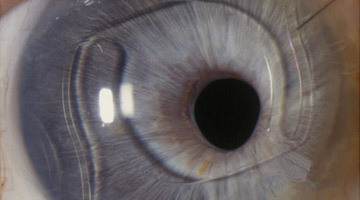

新一代后房睫状沟固定型人工晶体(Visian ICL),不管是矫治近视还是远视,在人工晶体中央都有一个小孔,以促进房水通过瞳孔流动。